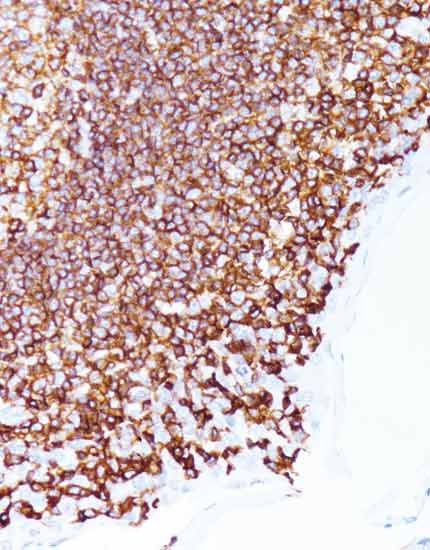

产品名称:CD99

产品编号:MAB-1012

阳性部位:细胞膜/细胞质

图片描述:

尤文氏肉瘤,CD99染色,细胞膜/细胞质阳性